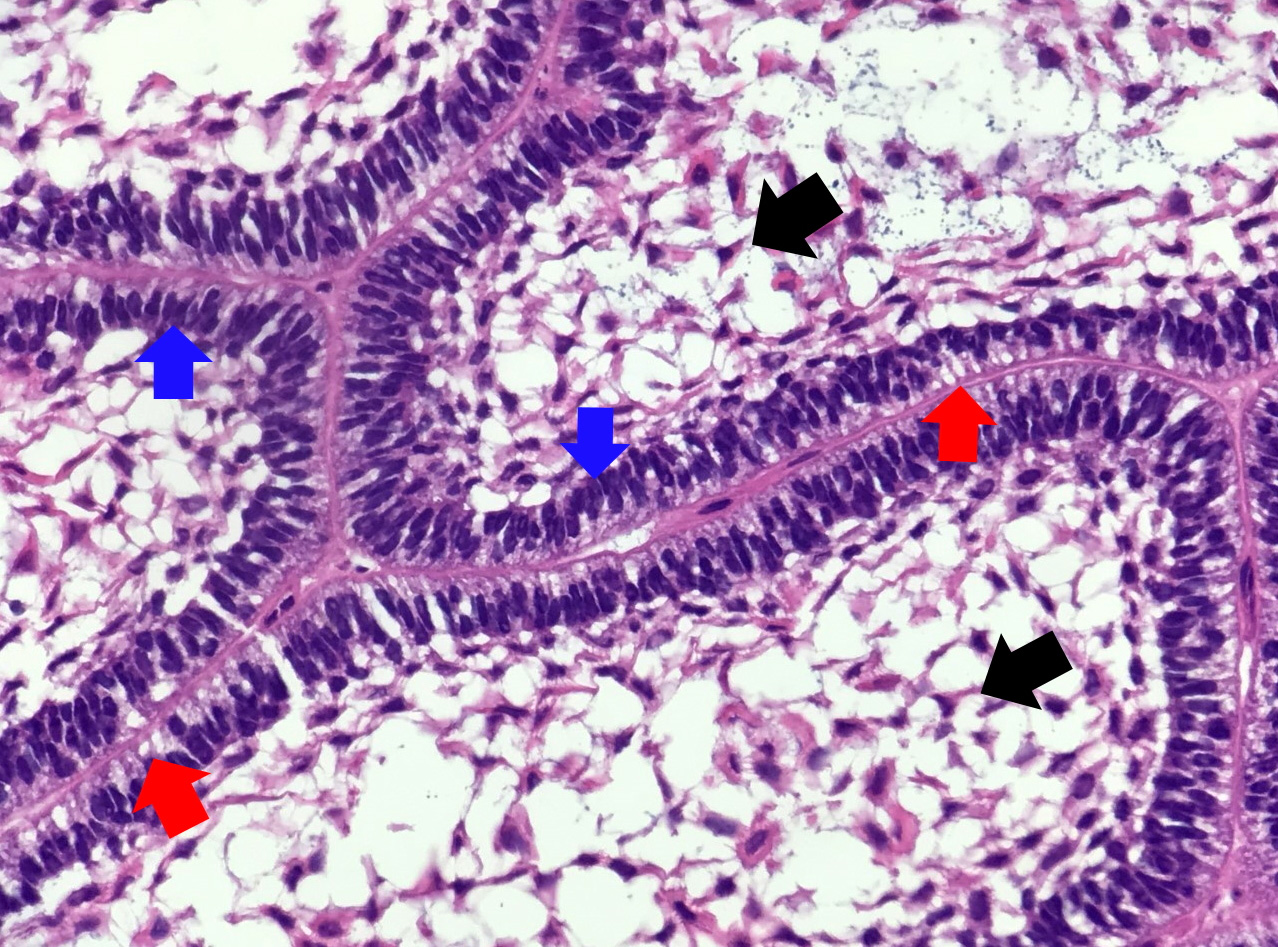

- Ameloblastoma, unicystic type has 3 histopathological patterns

- Single cystic lesion lined by ameloblastic epithelium that shows typical features of ameloblastoma in some areas, including columnar basal cells in palisading arrangement with vacuolated cytoplasm, hyperchromatic nuclei polarized away from basement membrane

- Suprabasal cells loosely textured and noncohesive resembling stellate reticulum, epithelial invagination, epithelial edema and separation

- Microscopic variants (may result in treatment differences - controversial)

- Luminal: cystic odontgenic epithelium with characteristic features (above) lining fibrous connective tissue wall

- Intraluminal: cystic odontgenic epithelium with characteristic features (above) lining fibrous connective tissue wall, with tumor extending into the cystic luminal space; may have intraluminal plexiform patterns

- Mural: cystic odontgenic epithelium with characteristic features (above) lining fibrous connective tissue wall but with the additional finding of definite ameloblastoma tumor islands within the fibrous connective tissue wall

Contributed by Kelly Magliocca, D.D.S., M.P.H. and Anne C. McLean-Holden, D.M.D., M.S.